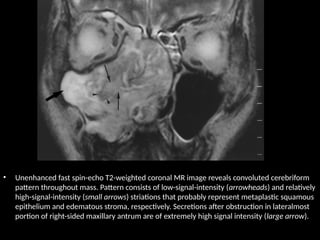

• Unenhanced fast spin-echo T2-weighted coronal MR image reveals convoluted cerebriform

pattern throughout mass. Pattern consists of low-signal-intensity (arrowheads) and relatively

high-signal-intensity (small arrows) striations that probably represent metaplastic squamous

epithelium and edematous stroma, respectively. Secretions after obstruction in lateralmost

portion of right-sided maxillary antrum are of extremely high signal intensity (large arrow).

• Unenhanced fastspin-echo T2-weighted coronal MR image reveals convoluted cerebriform pattern throughout mass. Pattern consists of low-signal-intensity (arrowheads) and relatively high-signal-intensity (small arrows) striations that probably represent metaplastic squamous epithelium and edematous stroma, respectively. Secretions after obstruction in lateralmost portion of right-sided maxillary antrum are of extremely high signal intensity (large arrow).